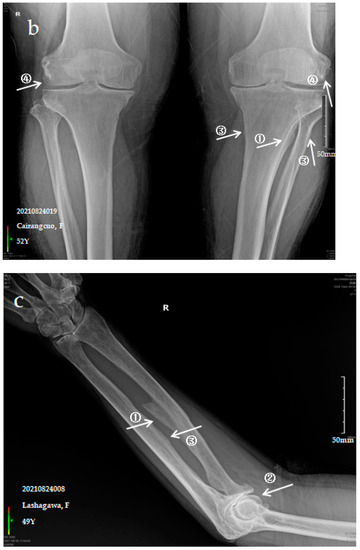

Figure 1.

X-ray imaging of SF patients. The anteroposterior actinogram of the upper limb (a) and both lower limbs (b) of patient with mild SF, the anteroposterior actinogram of the upper limb (c) and both lower limbs (d) of patient with moderate SF, the anteroposterior actinogram of the upper limb (e) and both lower limbs (f) of patient with severe SF. ①: ossification of interosseous membrane; ②: degeneration of the elbow joint; ③: Ossification shadow; ④: Ossification of knee joint capsule; ⑤: ossification of soleus tendon.

The patient is a 49-year-old female with pain in the limbs, neck and waist and limited ability to exercise with a variable impact on labour participation. The anteroposterior actinogram of the upper limb (Figure 1c) shows ossification of the interosseous membrane of the radius and ulna, with a fin-like appearance, degeneration of the elbow joint, ossification of the pronator teres muscle and bony protrusions on the inner side of the ulna. The anteroposterior actinogram of both lower limbs (Figure 1d) shows ossification of the tibiofibular interosseous membrane, a lacelike bony protrusion shadow at the tibial and fibular interosseous membrane, ossification of the long peroneal muscle, knee joint capsule and tibial collateral ligament.

3.2.3. Case Analysis of a Patient Diagnosed by X-ray with Severe SF

The patient is a 71-year-old male with severe bone and joint pain, limited activity and no ability to work. The anteroposterior actinogram of the upper limb (Figure 1e) shows obvious ossification of the interosseous membrane of the ulna and radius, forming a large fin-like ossification near the ulna and radius. The pronator teres muscle tendon shows obvious ossification, and a stalactite ossification shadow can be seen in the radial head. There is obvious degeneration of the elbow joint. The anteroposterior actinogram of both lower limbs (Figure 1f) shows ossification of the tibiofibular interosseous membrane, with a colliculus appearance. The peroneus longus tendons show obvious ossification, as do the soleus tendon, knee joint capsule and tibial collateral ligament.

Ossification of the interosseous membrane has a high incidence and specificity in SF and is one of the important diagnostic signs of SF. Ossification of the interosseous membrane was more obvious in patients with severe SF than in those with mild or moderate SF.